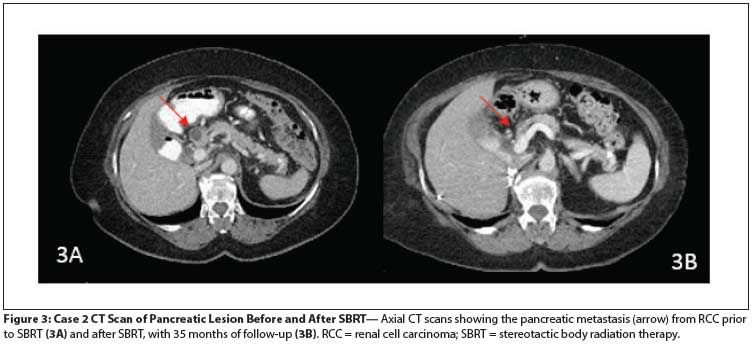

Figure 3: Case 2 CT Scan of Pancreatic Lesion Before and After SBRT

A growing subcarinal lesion and a 2.4-cm pancreatic lesion were noted on restaging CT scans. She underwent fine-needle aspiration biopsy of the pancreatic lesion and the specimen obtained was consistent with metastatic RCC. The pancreatic disease was first noted 5.5 years after the initial diagnosis. She underwent SBRT to the subcarinal lymph node and the pancreatic lesion; both were treated with 4,000 cGy in 10 fractions, at 400 cGy per fraction, given daily (Figure 1B). She had no symptoms subsequent to the SBRT treatment, and her pancreatic enzymes remained within normal limits.

After SBRT, and in light of her progressive disease, she was started on everolimus, but she developed drug-induced pneumonitis and the drug was discontinued. Pazopanib was administered, followed by axitinib, until she developed painful bone progression in the right humerus; on follow-up scans, the pancreatic lesion appeared atrophic, with a decrease in size to 10 × 6 mm and associated reduction in enhancement (Figure 3). She subsequently had a right proximal humerus resection of a 3.5-cm focus of metastatic RCC involving cancellous bone, and a prosthesis was placed. She was started on a phase I bevacizumab and programmed death ligand 1 (PD-L1) inhibitor protocol.

She later developed extensive pelvic bone disease, stopped systemic treatment, and underwent orthopedic surgery for disease stabilization before entering hospice care. With 3 years of follow-up after SBRT for her pancreatic lesion, there was no progression or development of any symptoms from this malignant deposit.